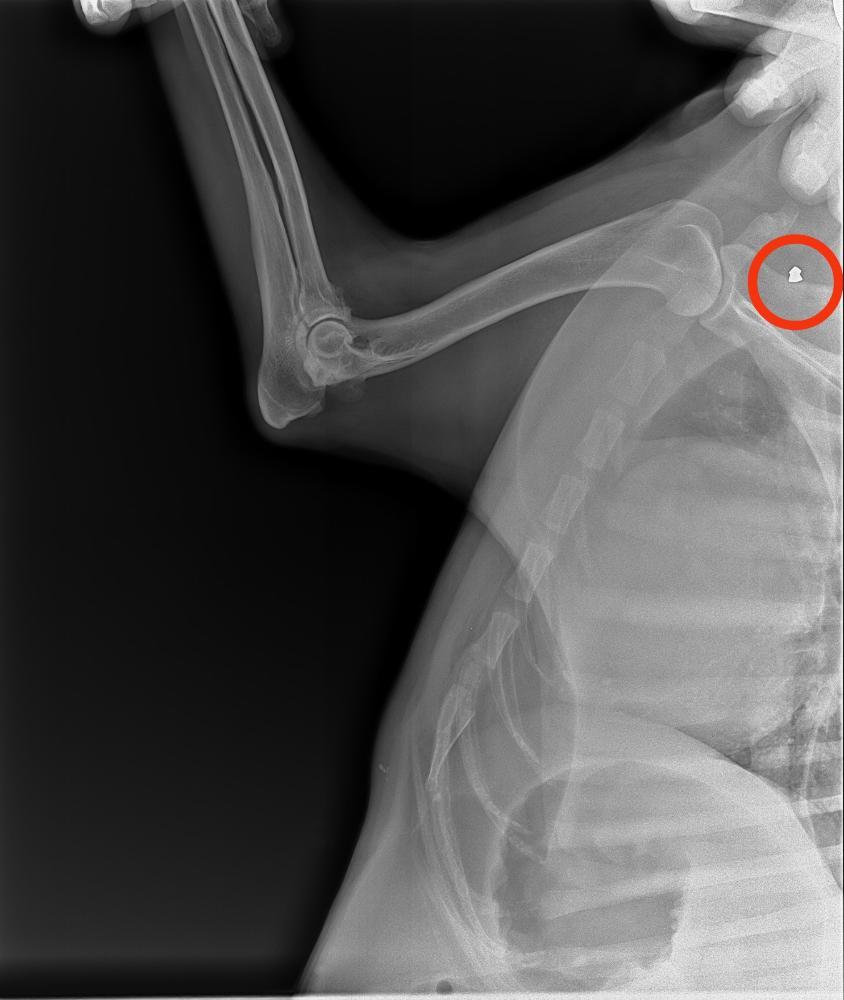

Elena_Tu Опубликовано 29 октября, 2025 Опубликовано 29 октября, 2025 Сделали снимки локтевых суставов, потому что Ники хромает на переднюю лапу. Артрит сильный, он болит. Но пока (учитывая ситуацию с ЖКТ) НПВС для обезболивания принимать нельзя. Проблема с желудком сейчас критичнее. На снимках случайно нашли пульку от травматического оружия в лопатке 🥲 не знаю, находили ли ее раньше, уже не помню всю предысторию. Но очень жаль мальчишку. Такой он трепетный, так его жалко. А там еще и пуля оказывается( 1